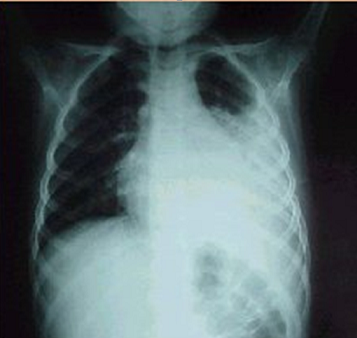

La neumonía es una infección del pulmón que puede ser ocasionada por: bacterias, virus u hongos.